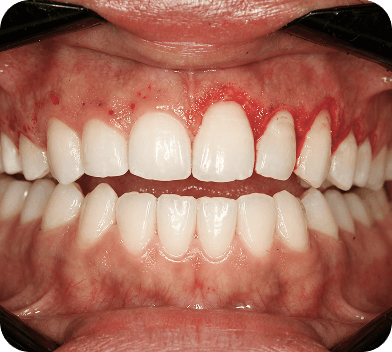

A periodontia é a área da odontologia responsável por prevenir e tratar doenças que afetam a gengiva e o osso de sustentação dos dentes, como a gengivite e a periodontite.

Essas doenças podem causar sangramento, mau hálito, retração gengival e, em casos mais graves, até a perda dos dentes.

Mas com o diagnóstico precoce e o tratamento correto, é possível restaurar a saúde bucal e evitar complicações.

Corrige o formato e contorno da gengiva, deixando o sorriso mais equilibrado. É ideal para quem tem retrações gengivais ou o chamado “sorriso gengival”, quando a gengiva aparece mais do que o desejado ao sorrir.